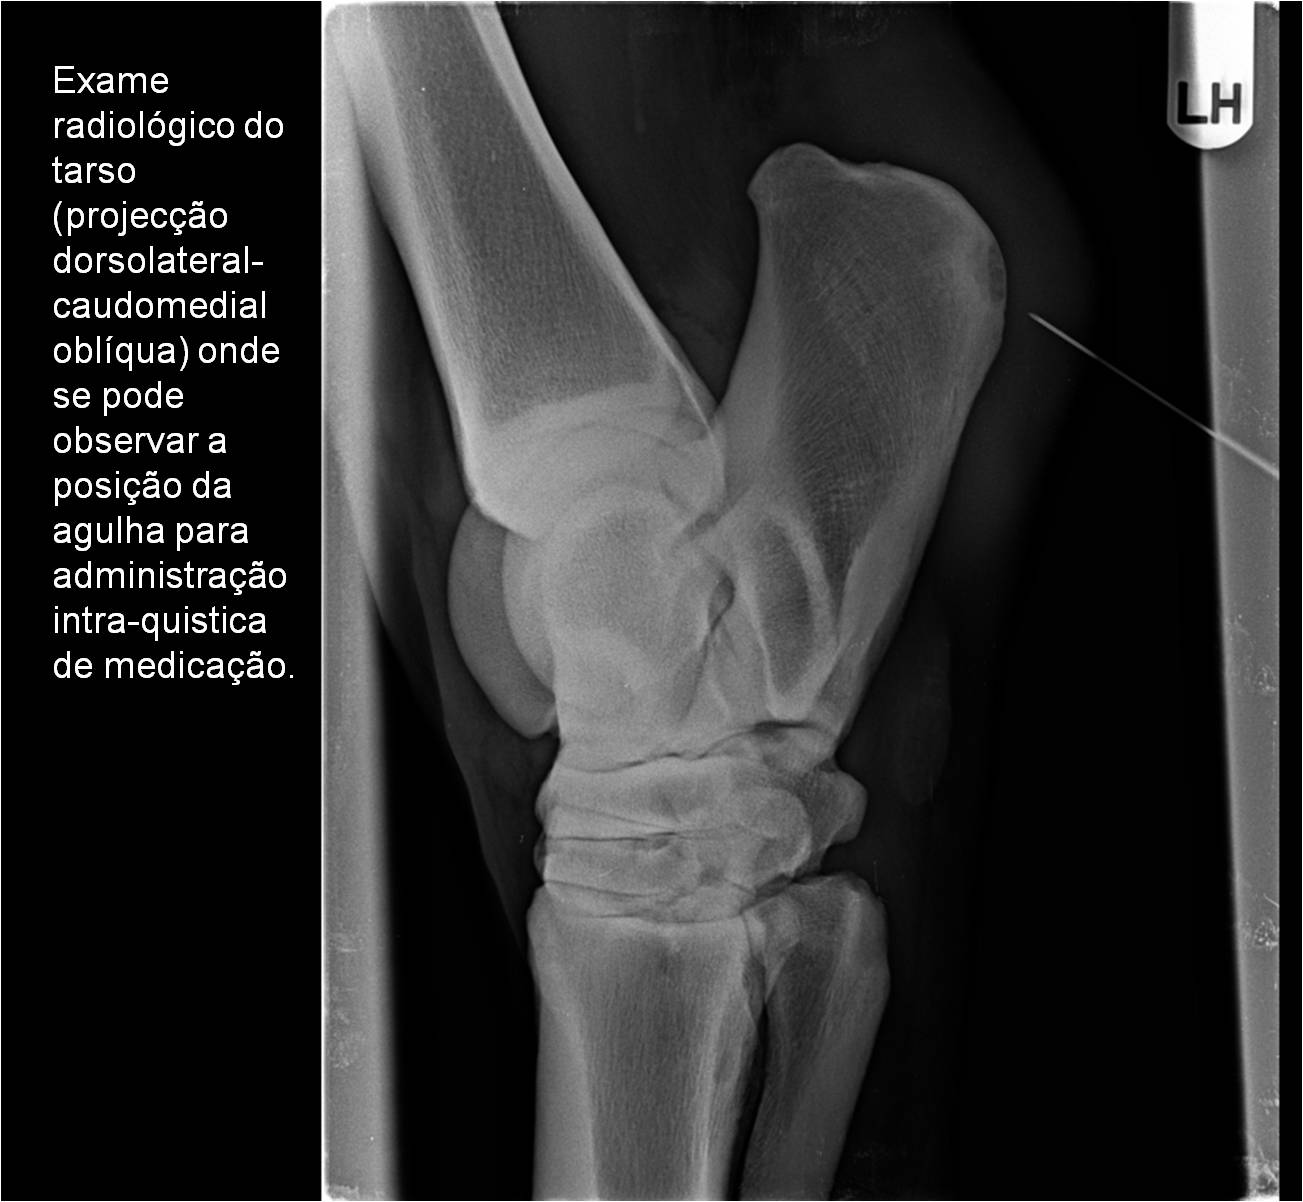

Publisher: Universidade de Évora

Abstract: O relatório de estágio encontra-se estruturado em três partes distintas. A primeira parte faz a caracterização das infraestruturas e funcionamento do Hospital Veterinário de Equinos de Lüsche, Oldenburg, Alemanha, assim como a análise casuística dos casos clínicos acompanhados durante os 6 meses de estágio. A segunda parte consiste de uma revisão bibliográfica sobre quistos do osso subcondral em equinos. Por fim, a terceira parte consta da apresentação e discussão de um caso clínico, nomeadamente o diagnóstico e acompanhamento imagiológico, por ressonância magnética, de um quisto subcondral na terceira falange num cavalo adulto; ### Abstract Equine Practice- Subcondral bone cyst of the third phalanx This internship report is divided in three parts. The first part characterizes the infrastructure and function of the Equine Hospital Lüsche, Oldenburg, Germany, as well as the casuistic of the clinical cases accompanied during the 6 month internship. The second part consists in a bibliographic review of cystic lesions of the subchondral bone in equines. The third part consists in a case report, the diagnostic and imagiological accompaniment, by use of magnetic resonance imaging, of a subchondral bone cyst in the distal phalanx of an adult equine.